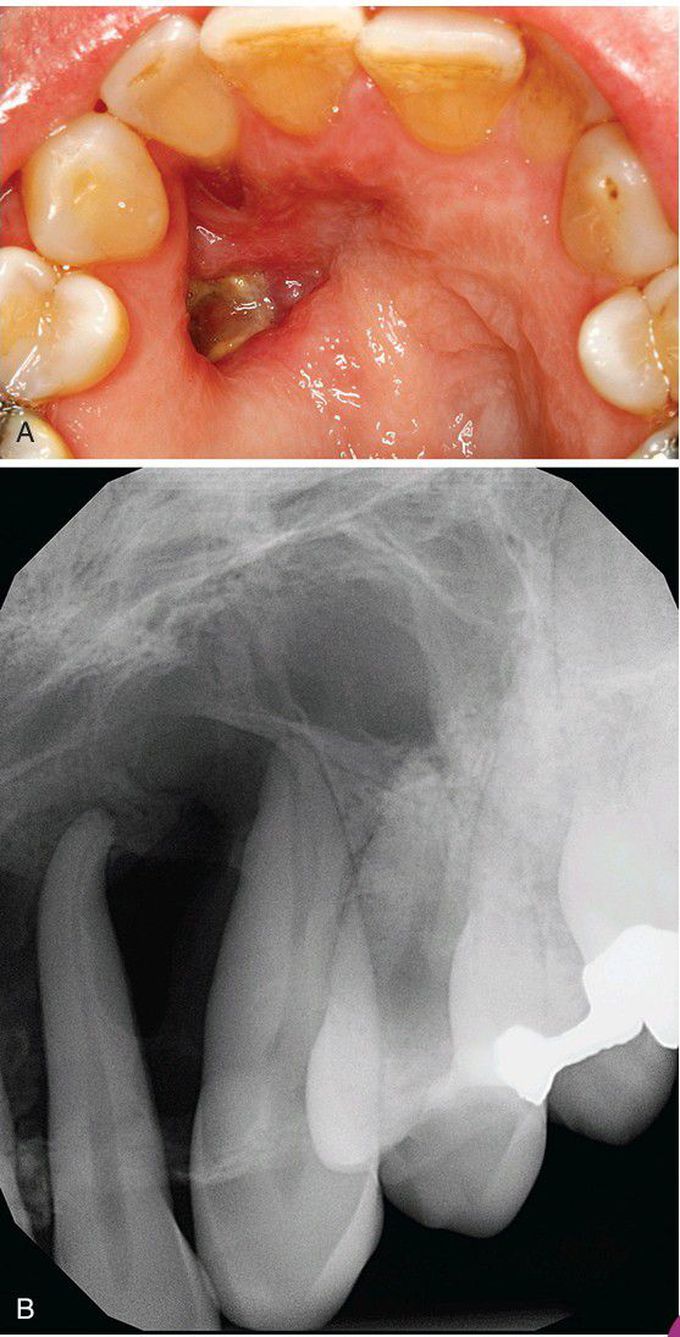

Odontogenic Fibroma

A, Clinical image showing a groove or defect in the palatal mucosa, a feature that has been described with maxillary lesions. B, Radiograph of this patient, depicting a multilocular radiolucency of the anterior maxilla.